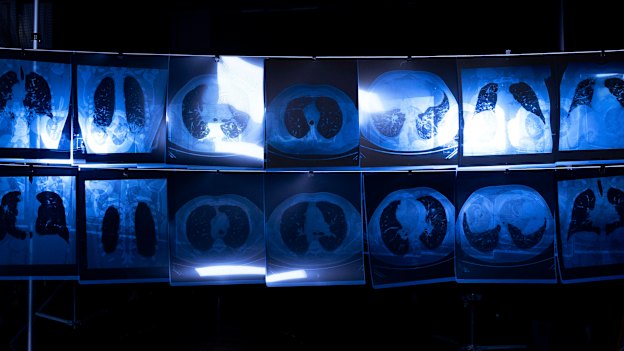

Professor Deborah Yates, a respiratory physician of 30 years, describes silicosis as an insidious disease. “It’s like being strangled ... like having your lungs contracting from inside,” she said. “It’s a sort of hidden scourge. You really need to get checked up with a chest CT because the other types of investigations are relatively insensitive, so they only pick up late disease.”